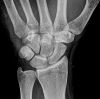

Handgelenk seitlich

Lagerung

Handgelenk, Unterarme, Ellenbogen (gebeugt) liegen mit der Kleinfingerseite streng seitlich auf. Handfläche hat leichte Retroflexion, d.h. der untere Handballen steht leicht vor. Daumen gestreckt über übrige Finger halten. Stellung durch Tasten im Handgelenk überprüfen.

Zentralstrahl

Senkrecht auf Handgelenk- und Filmmitte.

Anmerkung

Ulnar und Radius müssen distal übereinander projiziert werden. Os Scaphoideum und Os Lunatum liegen übereinander, ebenso die Mittelhandknochen, bei Verdacht auf Subluxation des Os Lunatums, Zusatzaufnahme in Flextion und Reflextion der Hand notwendig (Stressaufnahme).

Qualitätskriterien

Radius und Ulnar müssen deckungsgleich sein; Mittelhand, Handwurzelknochen und distaler Unterarm sollen abgebildet werden.